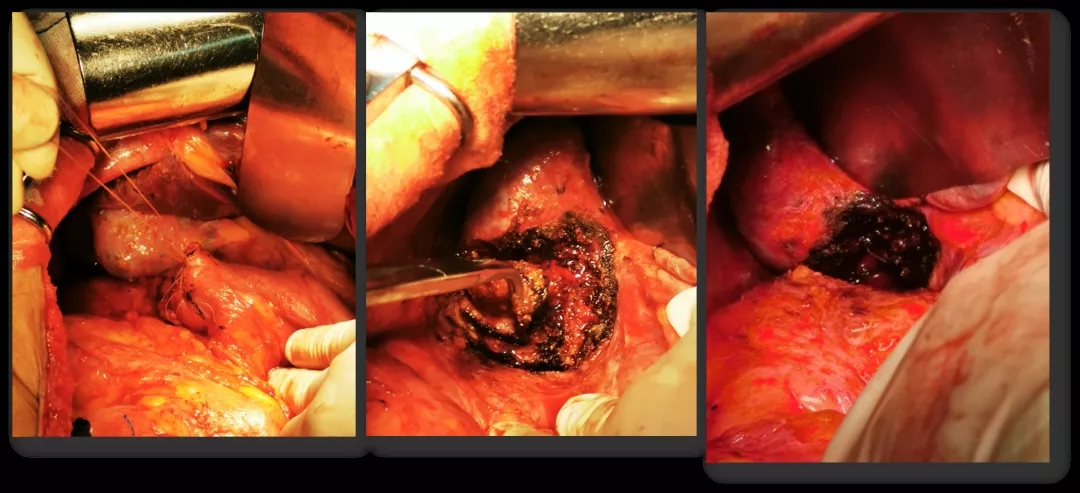

2016.10.26行三次减瘤术(乙状结肠部分切除侧侧吻合+腹盆腔减瘤+腹膜后淋巴结切除),术后无肉眼残留。

术中所见

2021.5.18行再次减瘤术(右肝部分切除+十二指肠修补术)。

再次减瘤术